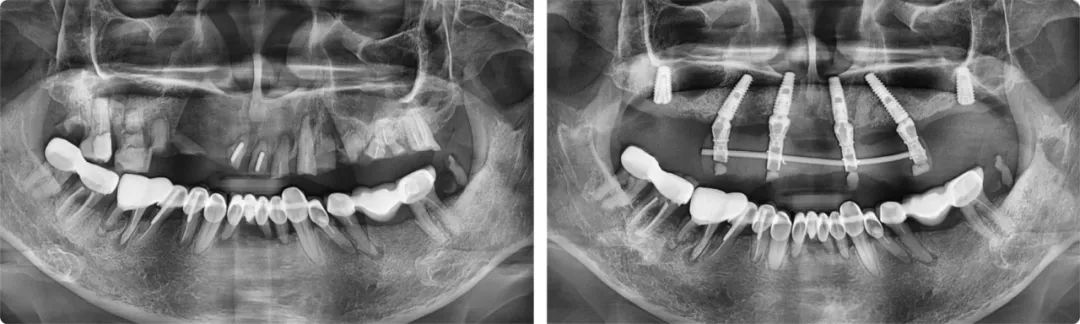

今年五月,葉宏接診了一位56歲的患者。這位患者的上半口全是牙齒殘根,骨量也不好,種植點(diǎn)位非常難選。一般情況下,上頜骨有6-8毫米的高度就可以滿足種植條件,但患者只有2-3毫米,風(fēng)險(xiǎn)較大,且種植位置靠近上頜竇,需要采用斜行植體,穿過(guò)兩個(gè)牙位,備孔時(shí)要斜著鉆,非常考驗(yàn)醫(yī)生的技術(shù)水平和臨床經(jīng)驗(yàn)。

為力求最佳的治療效果,葉宏為患者制訂了個(gè)性化的治療方案。“這例上半口種植由于情況特殊,不能一次性完成六顆牙的種植,我分了兩步完成。第一步是即拔即種,種4顆,然后清創(chuàng),等待恢復(fù),三個(gè)月后完成第二步,補(bǔ)種兩顆。”

患者術(shù)前術(shù)后全景片

葉宏解釋了這樣做的原因:標(biāo)準(zhǔn)的無(wú)牙頜種植上頜一般是6-8顆,下頜4-6顆,如果口腔條件允許,他會(huì)建議患者至少要種六顆,這樣牙槽骨受力更加均勻。如果只種四顆,后期的維護(hù)成本相對(duì)較高。分兩步走的治療方案雖然麻煩一些,但保障了種植牙的遠(yuǎn)離穩(wěn)定性。